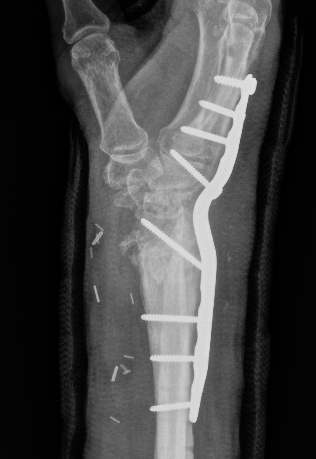

Undisplaced wrist fracture

- interrupts blood supply at a watershed area

- between 3 weeks and 3 months post injry